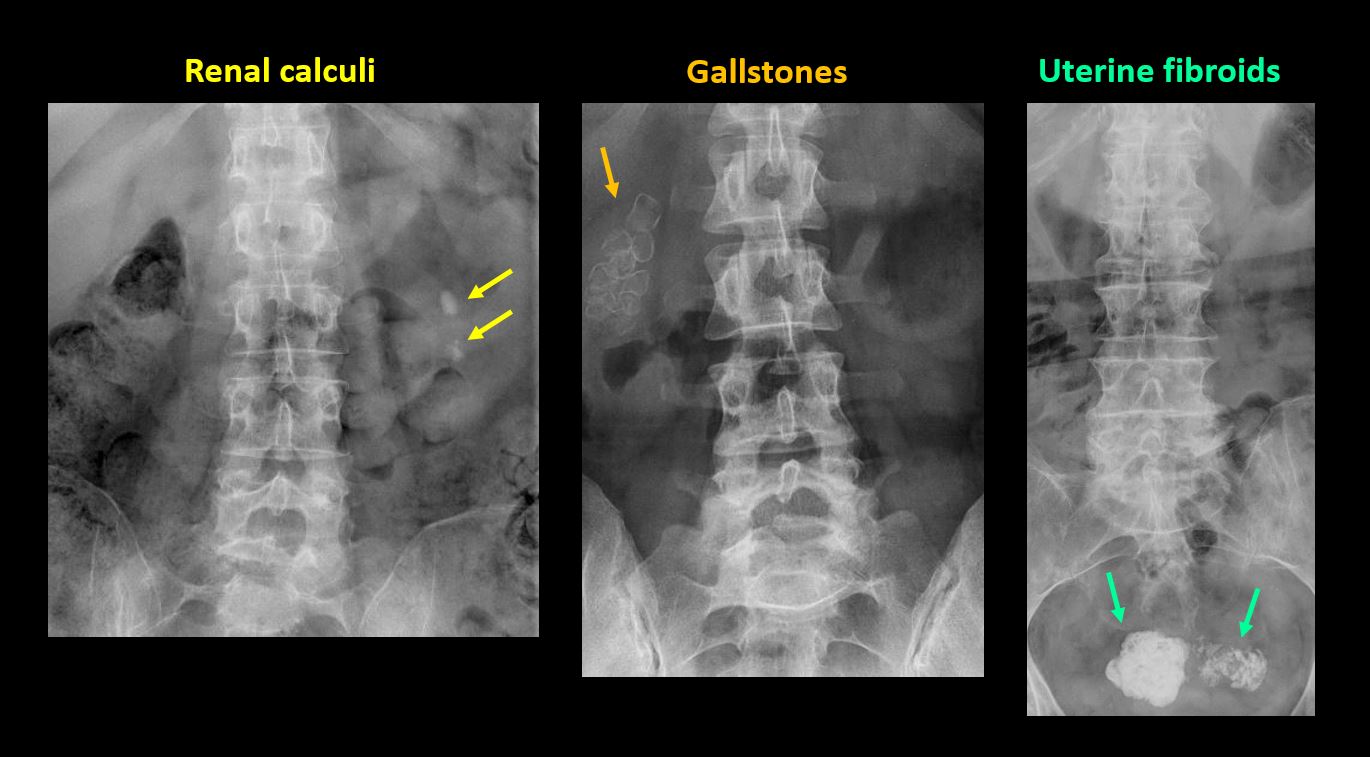

There are gallstones, vascular, renal, pelvic, or other soft tissue calcifications present. |

Yes | NA |